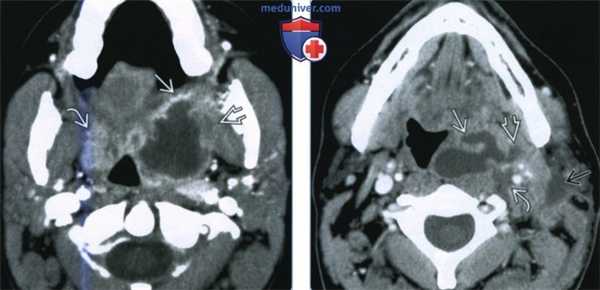

(Слева) При КТ с КУ в аксиальной проекции у ребенка с лихорадкой и жалобами на боли в горле видны увеличенные небные миндалины с характерной исчерченностью, типичные для негнойного тонзиллита.

(Справа) КТ с КУ в аксиальной проекции у ребенка с лихорадкой и жалобами на боли в горле. Обе небные миндалины увеличены и «целуются» у средней линии. В левой миндалине имеется явный участок пониженной плотности. При аспирации гноя получено не было, что говорит о наличии флегмоны.

(Слева) При КТ с КУ в аксиальной проекции определяется большой МА с содержимым пониженной плотности. Распространения в окологлоточное пространство за пределы капсулы миндалины нет. Левая миндалина увеличена и накапливает контраст, но признаков абсцедирования нет. Обратите внимание на сопутствующий выпот в заглоточном пространстве.

(Справа) При КТ с КУ в аксиальной проекции определяются миндаликовые абсцессы с обеих сторон, левый по размерам больше правого. Абсцессы сдавливают оба окологлоточных пространства, но распространения воспалительного процесса на окружающие структуры нет. Просвет дыхательных путей сужен и имеет щелевидную форму.

(Слева) При КТ с КУ в аксиальной проекции визуализируется левосторонний МА и ПТА, распространяющийся через капсулу миндалины в заднее щечное пространство и медиальную крыловидную мышцу жевательного пространства. Отмечается накопление контраста в правой воспаленной миндалине, но данных за абсцедирование здесь нет.

(Справа) При КТ с КУ в аксиальной проекции наблюдается осложненный левосторонний МА больших размеров. Инфекционный процесс распространился в сонное пространство В, в переднелатеральном направлении в верхнее поднижнечелюстное пространство, в латеральном направлении в нижние отделы пространства околоушной железы.